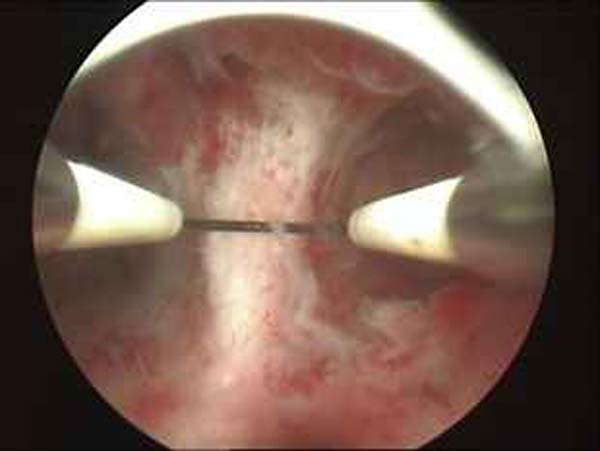

- Hysteroscopy Photos

Hysteroscopy Pictures | Dr N Layyous